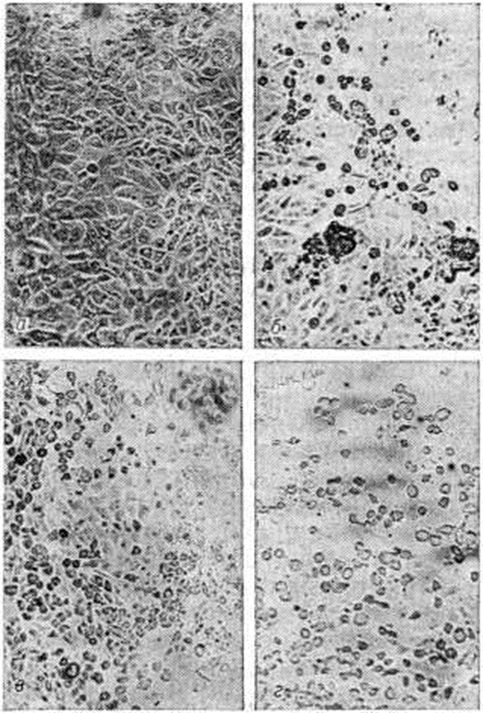

Эпидемиология. Источником инфекции при Полиомиелит является человек (больной или вирусоноситель). Вирус выделяется в окружающую среду с отделяемым из носоглотки и с фекалиями. Выделение вируса начинается на 2—4-й день после заражения. С отделяемым из носоглотки вирус выделяется в течение 1—2 недель, а с фекалиями — 4—7 недель Описаны случаи длительного выделения вируса с фекалиями — до 4 месяцев и более. Передача вируса происходит как фекально-оральным путём, так и, возможно, воздушно-капельным. Основное значение в эпидемический процессе при Полиомиелит имеет фекально-оральный механизм передачи инфекции, что обусловлено длительностью выделения вируса с фекалиями из инфицированного организма и высокой концентрацией вируса, которая может достигать нескольких миллионов частиц в 1 грамм фекалий. Попадание вируса Полиомиелит в организм человека относительно редко ведёт к развитию типичного заболевания — один случай болезни приходится на 100—1000 случаев бессимптомного вирусоносительства. Поэтому такие вирусоносители играют основную роль в распространении Полиомиелит Массивное выделение вируса с фекалиями в окружающую среду определяет возможность его распространения через воду, пищевые продукты, руки, мух. В сточных водах крупных населённых пунктов вирус Полиомиелит обнаруживается нередко в течение всего года. Обычные методы обработки сточных вод не всегда ведут к гибели вируса. Известны случаи выделения вируса Полиомиелит из водопроводной воды. Предполагается, что мухи, соприкасающиеся с фекалиями человека, могут стать механическими переносчиками вируса Полиомиелит Выявлена сохраняющаяся до 2—3 недель заражённость вирусом некоторых видов синантропных мух, отловленных в очагах Полиомиелит К факторам, способствующим распространению вируса Полиомиелит, относятся скученность населения, перенаселённость жилищ, отсутствие водопровода и канализации, нарушение санитарно-гигиенических правил, в первую очередь в детских учреждениях. Наиболее часто заболевания Полиомиелит регистрируются в летне-осенние месяцы (август — октябрь в странах сев. полушария и январь — апрель в странах южный полушария). Так, за 1950—1958 годы в СССР в I квартале года регистрировалось в среднем 9% годового числа заболеваний Полиомиелит, во II квартале — 16%, в III квартале — 50%, в IV квартале — 25%. В странах тропического пояса Полиомиелит регистрируется более равномерно в течение года, однако наблюдаются сезонные подъёмы заболеваемости. Патогенез. Преимущественным местом внедрения вируса Полиомиелит в организм является желудочно-кишечные тракт. Размножение вируса происходит в лимфоэпителиальных образованиях глотки и кишечника, где он определяется в высокой концентрации уже через 2—4 дня после заражения. Следующая стадия — вирусемия (смотри полный свод знаний) — соответствует началу препаралитического периода болезни, когда вирус может быть выделен из крови больных. С помощью иммунофлюоресценции (смотри полный свод знаний) вирус обнаруживается и в лейкоцитах, которые, возможно, играют роль в процессе его диссеминации во многие органы и ткани. Вирус размножается в лимфатических, узлах, селезёнке, печени, лёгких, иногда в почках и сердечной мышце. Стадия вирусемии заканчивается к концу препаралитического — началу паралитического периода. Механизм проникновения вируса в нервную систему через гематоэнцефалический барьер изучен недостаточно. Полагают, что вирус Полиомиелит проходит через эндотелий мелких сосудов, сосудистые сплетения, эпендиму желудочков; другим путём проникновения являются периферические нервы. Большая скорость продвижения вируса по нервам (2,4 миллиметров в час) свидетельствует о пассивном распространении вирионов по периневральным пространствам или через аксоплазму. Однако нельзя исключить возможность размножения вируса в нейролеммоцитах (шванновских клетках) и фибробластах эндотелиальной и периневральной оболочек. После проникновения вируса в центральная нервная система происходит его распространение по мозговому веществу, сопровождающееся повреждением двигательных клеток вплоть до их гибели. На протяжении 1—2 суток титр вируса в мозговом веществе нарастает, а затем начинает быстро снижаться, и вирус полностью исчезает. Клинически появление парезов и параличей (смотри полный свод знаний: Параличи, парезы) и динамика их развития совпадают с периодом максимального размножения вируса и его последующим исчезновением. Распространение вируса в нервной системе происходит по дендритам поражённых клеток и, возможно, через межклеточные пространства. Взаимодействие вируса и клетки включает несколько фаз: адсорбцию вируса на клетке, проникновение его в клетку, биосинтез вирусных компонентов, формирование вирусных частиц, некроз клеток. Однако возможна различная степень поражения мотонейронов, в том числе оно может быть обратимо. Синтез вирусных частиц происходит в цитоплазме клетки и сопровождается подавлением синтеза ДНК, РНК и белков клетки-хозяина. Первым морфологический выражением наступающих в нейроците изменений является нарушение структуры тигроида — базофильного компонента эргастоплазмы (тигролиз). Глубокие деструктивные изменения в клетке приводят к разрыву её наружной оболочки и выходу зрелого вируса в межклеточное пространство. Генетическими исследованиями установлена корреляция между паралитическим Полиомиелит и присутствием гаплотипа HL-A3 и HL-A7. Таким образом , тяжесть течения болезни определяется не только свойствами возбудителя, но и состоянием макроорганизма, в том числе его генетическими особенностями. Патогенез клинические, проявлений резидуального периода связан с гибелью двигательных нейроцитов спинного мозга и мозгового ствола, приводящей к денервации мышц, нарушению их трофики, выключению из произвольных движений. Длительное бездействие мышц, уменьшение их кровоснабжения, пребывание конечностей в неправильном положении лежат в основе перестройки анатомической структуры мышц, костей, суставов. Поражённые мышцы уменьшаются в размерах, замещаются жировой и соединительной тканью, сухожилия укорачиваются. Суставные хрящи истончаются, изменяется их цвет, теряется блеск, костная ткань атрофируется. Постепенно формируются мышечные и суставные контрактуры. В связи с избирательным поражением одних мышц и сохранностью других изменяется их нормальное физиологический взаимоотношение, что служит причиной патологический положения туловища и конечностей, их деформации. Влияние физической нагрузки, например, длительное вертикальное положение тела, ходьба, усугубляет имеющуюся патологию мышц, костей и суставов и влечет за собой компенсаторные изменения в непоражённых мышцах. В развитии контрактур и деформаций играют роль и трофические расстройства, приводящие к задержке роста конечностей, их укорочению. Неравномерное восстановление функции мышц может являться причиной деформации костей. Патологическая анатомия. При макроскопическом исследовании центральной нервной системы обращает на себя внимание полнокровие сосудов вещества и поверхности спинного мозга; полнокровие особенно выражено в сером веществе, которое на поперечных разрезах имеет набухший вид. Наиболее выраженные морфологический изменения при Полиомиелит обнаруживают в спинном и продолговатом мозге, в мосту головного мозга, среднем и промежуточном мозге, в предцентральных извилинах коры большого мозга. Поражению и гибели нейроцитов предшествует ряд изменений, которые принято рассматривать как изменения препаралитического периода Полиомиелит Они изучены при морфологический исследовании нервной системы людей, умерших в ранние сроки заболевания, и в экспериментах на животных. К самым ранним изменениям относят полнокровие сосудов, отёк эндотелия капилляров и сосудов спинного мозга, паутинной оболочки, её круглоклеточную инфильтрацию (цветной рисунок 1), хроматолиз в нейроцитах (цветной рисунок 2), гипертрофию и пролиферацию глиальных макрофагов (смотри полный свод знаний). В нейронах, клетках нейроглии — астроцитах, олигодендроглиоцитах, в эндотелии сосудов и макрофагах обнаруживают вирус в виде кристаллоподобных и массивных скоплений зрелых вирионов с вирусным матриксом. Вирусные включения обычно располагаются в околоядерных и периферических участках нейроплазмы этих клеток. После внедрения вируса в нейроциты развиваются дистрофические, а затем сочетающиеся с ними некротические процессы с полным распадом всех ультраструктур, в том числе и ядерной мембраны, а также процессы, связанные с репродукцией вируса. В первые дни после появления параличей выявляются полнокровие сосудов и умеренно выраженный отёк вещества спинного и головного мозга, небольшое расширение желудочков мозга, гиперемия сосудов спинного и продолговатого мозга, моста головного мозга, особенно в области покрышки, отёк стенок и эндотелия сосудов, стаз (смотри полный свод знаний), кровоизлияния, периваскулярные круглоклеточные инфильтраты, резко выраженная гипертрофия и гиперплазия (диффузная и очаговая) глиоцитов, выпадение, то есть исчезновение, нейроцитов, особенно в передних рогах спинного мозга (цветной рисунок 3 и 4), а также круглоклеточная инфильтрация паутинной оболочки спинного мозга. В эти же сроки наблюдается инфильтрация серого вещества спинного мозга полиморфно-ядерными лейкоцитами, а также скопление их в участках полного и неполного некроза (цветной рисунок 5) серого вещества, в которых обнаруживают глиальные макрофаги, гипертрофированные астроциты, зернистые шары (смотри полный свод знаний) (цветной рисунок 6). Особенно много глиальных макрофагов встречается в местах выпадения нейроцитов. В оставшихся нейроцитах наблюдается хроматолиз (смотри полный свод знаний: Нервная клетка), резкое уменьшение содержания в нейроплазме РНК, нейронофагия (смотри полный свод знаний) и псевдонейронофагия (цветной рисунок 7). Рядом с такими нейроцитами могут быть обнаружены глиальные макрофаги. Многие нейроциты приобретают вид клеток-теней, около них нередко наблюдается скопление глиоцитов, принимающих участие в процессе нейронофагии (цветной рисунок 8). В ядрах нейроцитов иногда встречаются одиночные и расположенные группами оксифильные и базофильные включения размерами 0,8—2,4 микрометров. Гибель нейроцитов сопровождается распадом синапсов, валлеровским перерождением нервных волокон передних корешков спинномозговых нервов, а также спинномозговых и черепно-мозговых нервов (смотри полный свод знаний: Валлера перерождение). Воспалительные изменения с периваскулярными круглоклеточными инфильтратами, нейронофагией и псевдонейронофагией обнаруживают также в спинномозговых узлах и чувствительных узлах черепно-мозговых нервов. При гибели большого числа нейроцитов ядер черепно-мозговых нервов и ретикулярной формации мозгового ствола развиваются нарушения центральной регуляции дыхания и кровообращения. Структура большинства сохранившихся нейроцитов чаще всего восстанавливается в течение первого месяца после острого периода заболевания. Периваскулярные круглоклеточные инфильтраты, в составе которых обнаруживаются лимфоциты и плазматические клетки, скопления астроцитов и глиальных макрофагов — глиальные узелки (цветной рисунок 9) в некоторых случаях могут быть обнаружены при морфологический исследовании центральная нервная система через 3½—4 месяцев На мес те погибших нейроцитов развивается изоморфный и анизоморфный глиоз (смотри полный свод знаний), в области очагов некроза — глиомезодермальные рубцы. У умерших от Полиомиелит отмечают гиперплазию одиночных и групповых лимфатических, фолликулов слизистой оболочки тонкой кишки, лимфатических, узлов, селезёнки (иногда с умеренной спленомегалией), дистрофические изменения миокарда, печени, почек; в ряде случаев обнаруживают пневмонию, ателектазы лёгких. Для вирусологического исследования на вскрытии берут ткань головного и спинного мозга, кровь, цереброспинальную жидкость, содержимое кишечника. Иммунитет. В результате заражения вирусом Полиомиелит в организме развивается гуморальный и местный тканевой иммунитет (смотри полный свод знаний). В сыворотке крови обнаруживают нейтрализующие, комплементсвязывающие и преципитирующие антитела (смотри полный свод знаний). Нейтрализующие антитела появляются вскоре после заражения, часто ещё до начала болезни, и сохраняются на протяжении всей жизни. Комплементсвязывающие антитела возникают в первые 3 недель болезни и исчезают в течение нескольких ближайших лет. Преципитирующие антитела определяются уже на 1—2-й недель болезни, затем титр их резко снижается, и через 3—4 месяцев они исчезают. Материнские антитела передаются ребёнку и сохраняются первые 3—6 месяцев жизни. Пассивно введённые антитела остаются в крови лишь 3—5 недель Антитела при Полиомиелит носят типоспецифический характер, но заражение вирусом одного типа может вести к появлению в низких титрах гетерологичных антител, обычно быстро исчезающих. Роль антител, циркулирующих в крови, сводится главным образом к нейтрализации вируса в период вирусемии и к предупреждению, таким образом, проникновения вируса в нервную систему. Иммуногенез при Полиомиелит включает как гуморальные, так и клеточные факторы иммунитета. Вместе с тем не удаётся установить прямой зависимости между титрами антител в крови и размножением вируса Полиомиелит в нервной системе, где антитела либо отсутствуют, либо имеют низкие титры, не определяемые обычными методами. Тем не менее уже через 1—2 дня после проникновения вируса в нервную систему количество его начинает быстро снижаться, и вскоре вирус исчезает. У обезьян, заражённых интрацеребрально и не имеющих антител в крови, вирус в центральная нервная система обнаруживается в те же сроки, что и у обезьян с высокими титрами антител. Приведённые факты дали основание считать, что, кроме гуморального иммунитета, развивается местная тканевая резистентность, не зависящая от концентрации антител в крови. Механизм указанного явления изучен недостаточно. Одним из факторов кишечной резистентности считается наличие в кишечнике вируснейтрализующих антител, относящихся к IgA. Высказывается также гипотеза о выработке ингибитора, способного тормозить размножение вируса, в частности в нервной ткани. Иммунитет при Полиомиелит имеет стойкий характер. Однако, учитывая, что он является типоспецифическим, возможно повторное заболевание Полиомиелит при заражении вирусом другого типа. При специфической профилактике Полиомиелит живой вакциной, приготовленной из трёх типов вируса Полиомиелит, создаётся достаточно стойкий иммунитет к заражению (смотри полный свод знаний: ниже раздел Профилактика). Клиническое течение. Инкубационный период длится от 2 до 35 дней, чаще 10—12 дней. Клинические, классификация Полиомиелит основана на современном представлении о патогенезе болезни, в соответствии с которым инфекционные процесс при Полиомиелит имеет этапное развитие: размножение вируса в лимфоэпителиальных образованиях глотки и кишечника, вирусемия, проникновение вируса в нервную систему. На каждом из этапов процесс может остановиться. В зависимости от этого развивается: инаппарантный Полиомиелит (вирусоносительство); Полиомиелит без поражения нервной системы (абортивный, или висцеральный); Полиомиелит с поражением нервной системы (непаралитический, или менингеальный, и паралитический). По степени выраженности клинические, симптомов течение Полиомиелит может быть лёгким, среднетяжёлым и тяжёлым. Инаппарантный полиомиелит представляет собой вирусоносительство, в основе которого лежит размножение вируса в лимфоэпителиальных образованиях глотки и кишечника без клинические, проявлений болезни. Случаи инаппарантного Полиомиелит встречаются значительно чаще клинически выраженных форм. Абортивный полиомиелит характеризуется развитием вирусемии и клинически проявляется лихорадкой, умеренной интоксикацией, слабостью, небольшой головной болью, иногда умеренными катаральными явлениями, гиперемией зева, дисфункцией кишечника. Клинические признаки поражения нервной системы и воспалительные изменения цереброспинальной жидкости отсутствуют. Течение этой формы Полиомиелит благоприятное, выздоровление наступает через 3—7 дней.